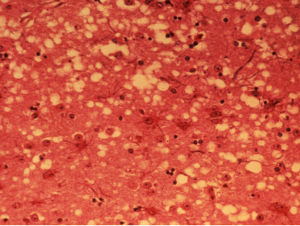

牛海綿狀腦病俗稱瘋牛病(mad cow disease),是由傳染因子引起的牛的一種進行性神經系統的傳染性疾病,是一種傳染性海綿狀腦病。該病的主要特徵是牛腦發生海綿狀病變,並伴隨大腦功能退化,臨床表現為神經錯亂、運動失調、痴呆和死亡。

在研究室中,人們研究了牛腦組織上的小“洞”( ·1996年3月20日,英國政府承認出現瘋牛病病例,且證實和人類“感染性海綿狀腦病(Transmissible spongiform encephalopathies)”有關(即“瘋牛病事件”),鏇即造成歐洲、亞洲、非洲眾多國家的恐慌,並開始全面停止英國牛肉及相關產品的引進,使英國的農牧業受到一定程度的打擊。除了對英國及英國牛肉的主要進口國造成風暴外,對不進口或是較少進口英國牛肉的國家或地區也有一定衝擊。英國發現的瘋牛病病例占了全球的95%以上。(當年英國首相約翰·梅傑)